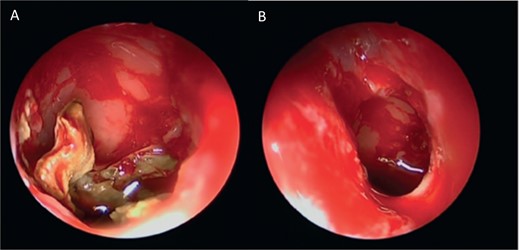

Intra-operative endoscopic view showing (A) polyps in the left osteomeatal complex with (B and C) fungal mud and mucin.

A 37-year-old female with a history of bronchial asthma, complained mainly of chronic headache, left sided facial pain, which was associated with persistent post-nasal drip. Endoscopic examination showed left-sided tenacious discharge filling the middle meatus with grade two polyps. NCCT (Fig. 5) showed left isolated heterogenous maxillary sinus opacity suggestive of allergic fungal sinusitis. She underwent endoscopic sinus surgery (Fig. 6) with removal of fungal mucin and mud, complete left maxillary sinus aeration was ensured. The patient was free of symptoms during her 1 week follow up.